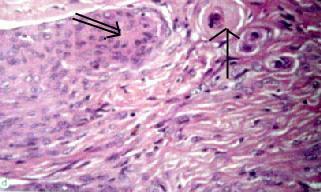

Meningothelial

meningioma (H&E): meningothelial cells and

fibrous areas with attempts at whorl formation (doublearrow)

and psammoma bodies(arrow).